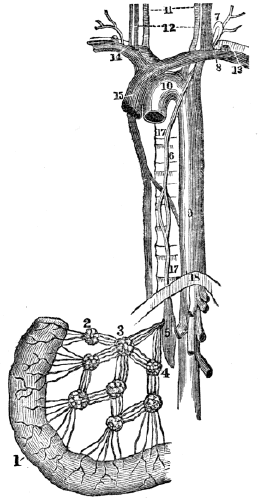

| 20. | Anatomy of the Lymphatic Vessels, | 181 |

| 20. | Physiology of the Lymphatic Vessels, | 183 |

| 20. | Hygiene of the Lymphatic Vessels, | 188 |